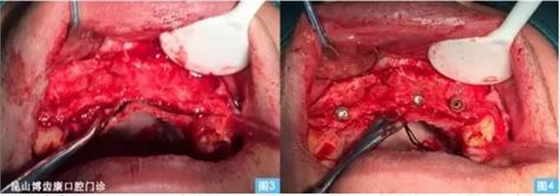

圖3圖4:(左圖3)牙槽嵴頂偏腭側(cè)水平切口,雙側(cè)附加切口翻開全厚粘骨膜瓣至鼻底,清晰暴露術(shù)區(qū)。(右圖4)小球鉆定位,擴(kuò)孔鉆依次備洞,植入植體 ,可見13、23唇側(cè)骨壁缺損嚴(yán)重 。